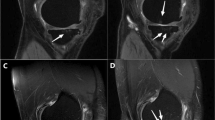

The control group’s tissue specimens revealed histologically a single-stratum to three-strata synovial intima connected by a loose connective tissue with a few narrow vessels (depending on the wall thickness) (Fig. 1a) [22, 23].

HE Staining of soft tissue. a Synovial tissue from the control group. Intima has one to three strata, loose connective tissue, superficial network of capillaries connected to the intima. b AF tissue from a patient. Synovial hyperplasia, enlarged subintima with vascular infiltration, fibrosis. c β catenin expression in a patient’s AF tissue. d AF tissue exhibits macrophages in the intima with typical immunohistological staining for CD68 in close vicinity to vessels. AF arthrofibrosis

Arthrofibrosis

The patients with AF revealed obvious intimal hyperplasia in the synovia with more than three cell layers (Fig. 1b). The adjacent subintima is fibrotic, as evident through increased presence of fibroblasts and fibrocytes. In addition to the subintimas being hypervascular, the vessel walls are morphologically too thick (Fig. 1b). Areas of manifest fibrosis have become attached to the fibrotic subintima with no signs of vascularization. Immune staining with β-catenin displays different numbers of β-catenin-positive fibroblasts (Fig. 1c).